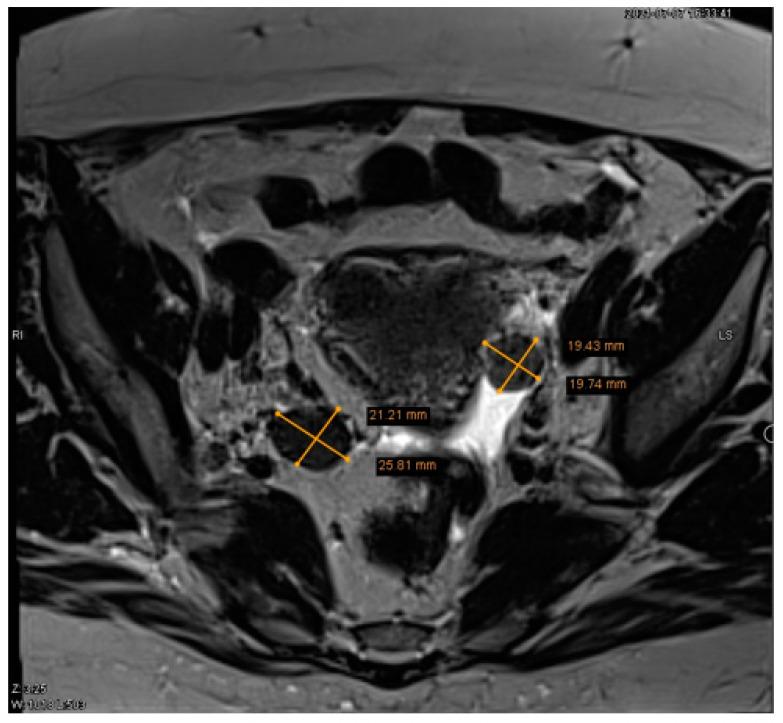

Ovarian Leydig cell tumor is a rare type of ovarian steroid cell neoplasms, presenting in only 0.1% of all ovarian tumor cases, and is generally androgen-secreting and unilateral. Although they are often malignant non-spreading tumors, which have excellent prognosis, benign ovarian Leydig cell tumors with low-risk malignancy can be also detected. Ovarian hyperthecosis is a rare non-neoplastic disorder, in most cases bilateral. Ovarian tumors and ovarian hyperthecosis are one of the main causes of hyperandrogenism in postmenopausal women, a condition strongly associated with both hormonal and metabolic changes. Here, we report a 65-year-old patient with complaints of excessive body hairiness and alopecia. The laboratory investigation showed increased levels of serum testosterone and dehydroepiandrosterone sulfate (DHEA-S). Imaging, including transvaginal ultrasound and pelvic MRI revealed the presence of two masses in the ovaries. The patient underwent a laparoscopic bilateral salpingo-oophorectomy due to the ovarian tumors unknown etiology, and histopathological examination revealed a unilateral benign left ovarian Leydig cell tumor with bilateral ovarian stromal hyperplasia and ovarian hyperthecosis. Making differential diagnosis between ovarian tumors and ovarian hyperthecosis is difficult. Bilateral salpingo-oophorectomy is the treatment of choice in postmenopausal women with benign Leydig cell ovarian tumor, as well as ovarian hyperthecosis, as it offers both a cure and diagnostic confirmation.

卵巢睾丸间质细胞瘤是一种罕见的卵巢类固醇细胞瘤,仅占所有卵巢肿瘤的 0.1%,通常为雄激素分泌且单侧发生。虽然它们通常是恶性非扩散性肿瘤,具有良好的预后,但也可以检测到具有低恶性风险的良性卵巢睾丸间质细胞瘤。卵巢卵泡膜细胞瘤是一种罕见的非肿瘤性疾病,大多数情况下为双侧发生。卵巢肿瘤和卵巢卵泡膜细胞瘤是绝经后妇女高雄激素血症的主要原因之一,这种情况与激素和代谢变化密切相关。在此,我们报告了一例 65 岁患者,主诉多毛和脱发。实验室检查显示血清睾酮和硫酸脱氢表雄酮(DHEA-S)水平升高。影像学检查,包括经阴道超声和盆腔 MRI,显示卵巢内存在两个肿块。由于卵巢肿瘤病因不明,患者接受了腹腔镜双侧输卵管卵巢切除术,组织病理学检查显示左侧良性卵巢睾丸间质细胞瘤伴双侧卵巢间质增生和卵巢卵泡膜细胞瘤。区分卵巢肿瘤和卵巢卵泡膜细胞瘤具有一定难度。对于良性卵巢睾丸间质细胞瘤和卵巢卵泡膜细胞瘤的绝经后妇女,双侧输卵管卵巢切除术是治疗的首选方法,因为它既能治愈又能提供诊断依据。